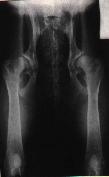

Zdravé kloubyTěžká DKK

Na levém snímku můžeme vidět kyčelní klouby zdravého zvířete, ale na druhém snímku je zrentgenované zvíře postižené těžkou dysplazií.